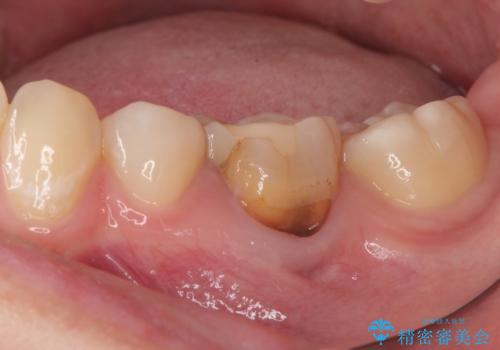

- 神経を取り除いた後に歯の色が変色して気になってきたとのことで来院された患者様です。

奥歯も著しく茶色に変色していたため、同様にオールセラミッククラウンにて補綴治療を行うこととしました。